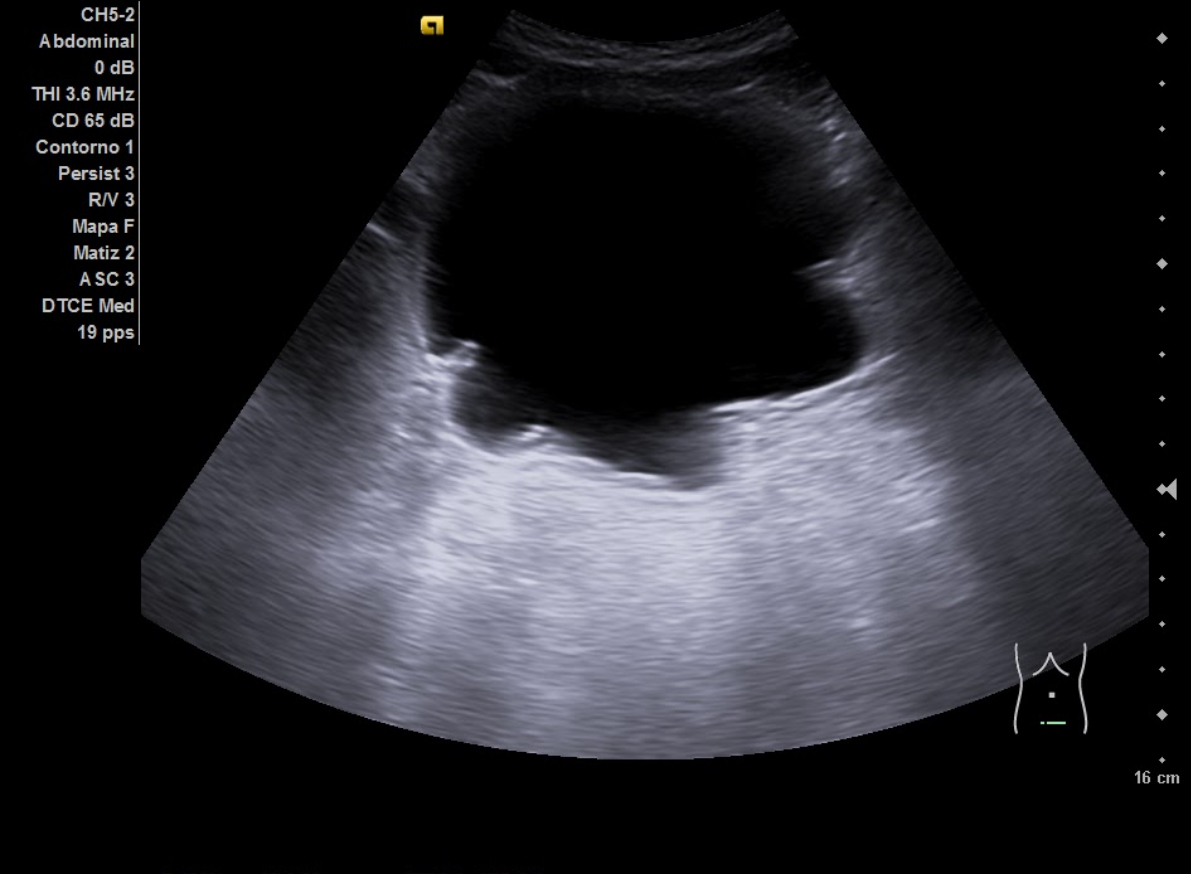

Ecografía aparato urinario en Centro de Salud: Riñones de tamaño normal, parénquima conservado con dilatación pielocalicial grado II-III izquierdo y grado II derecho. Vejiga con aspecto trabeculado, pared irregular con divertículos. Volumen premiccional 550 cc, postmiccional 450 cc. Volumen prostático de 50 cc.